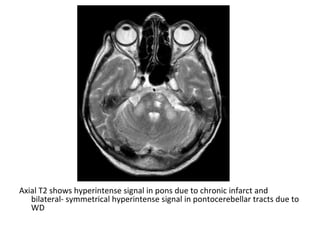

Axial T2 shows hyperintense signal in pons due to chronic infarct and

bilateral- symmetrical hyperintense signal in pontocerebellar tracts due to

WD

T2 showing bilateral symmetrical high signal in both cerebellar